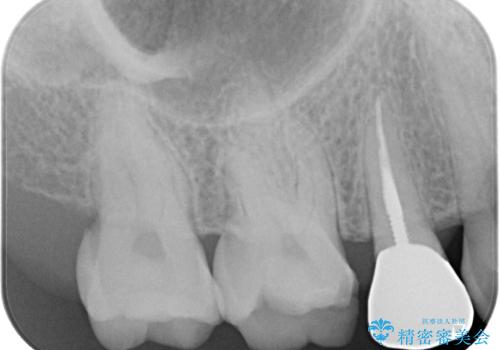

- 笑うときに目立つ銀歯を白くしたいとのことで来院された患者様です。

奥歯ではありますが、以前抜歯矯正をされているので前の方へ移動しており、非常に目立っていました。

仮歯に替えた上で、速やかにオールセラミッククラウンにて補綴治療を行うこととしました。

銀歯を外したところ、土台にほとんどむし歯はなかったため、土台のやり替えを行うことなく、セラミッククラウンを装着しました。